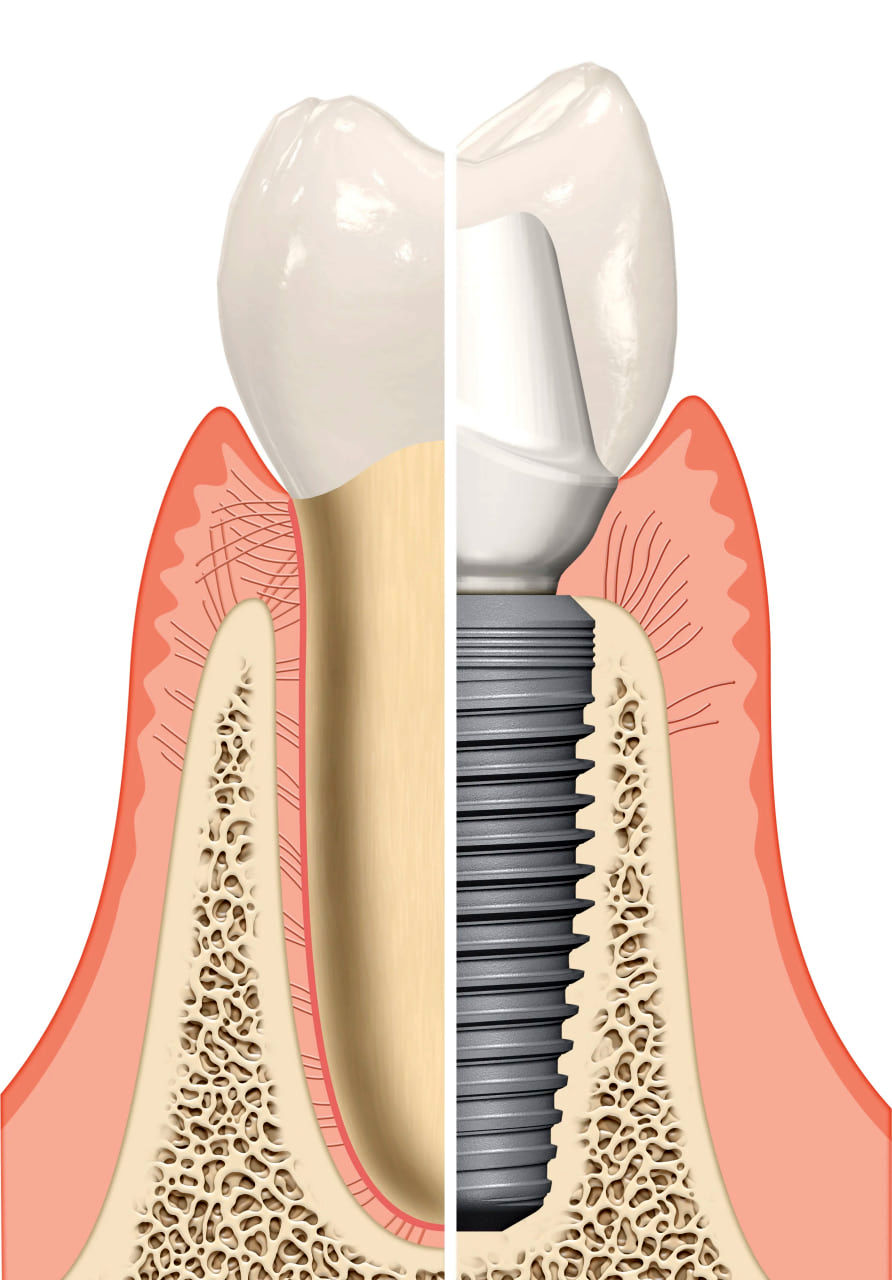

کاشت دندان طبیعی که با نام ایمپلنت دندان نیز شناخته می شود، یک روش جایگزینی دندان از دست رفته است که به علت اینکه یک پایه تیتانیومی دارد که مانند ریشه دندان به استخوان فک جوش می خورد و شباهت زیادی به دندان طبیعی دارد، به نام کاشت دندان طبیعی شناخته می شود.

کاشت دندان طبیعی یا همان ایمپلنت دندان، یکی از پیشرفتهترین روشهای جایگزینی دندانهای از دسترفته است که طی سالهای اخیر با پیشرفت علم دندانپزشکی دیجیتال، دقت و موفقیت آن به طرز چشمگیری افزایش یافته است. در این روش، پایهای از جنس تیتانیوم خالص — که کاملاً با بدن انسان سازگار است — درون استخوان فک کاشته میشود. این پایه همانند ریشهی دندان طبیعی عمل میکند و پس از جوش خوردن کامل با استخوان فک (فرایندی به نام اُسیوانتگریشن)، تاج یا روکش دندان روی آن قرار میگیرد. نتیجه نهایی، دندانی است که از نظر زیبایی، عملکرد و حس جویدن، تقریباً تفاوتی با دندان واقعی ندارد.

کاشت دندان طبیعی میتواند جایگزینی دائمی و بدون نیاز به تراش دندانهای مجاور باشد. برخلاف روشهای قدیمی مانند بریج، ایمپلنت باعث تحلیل استخوان فک نمیشود و حتی به حفظ تراکم استخوان نیز کمک میکند. همین ویژگی باعث شده که این روش، محبوبترین درمان برای دندانهای از دسترفته در سراسر دنیا باشد.